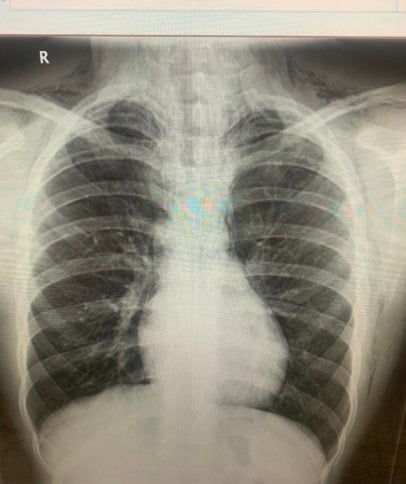

没想到过后利特乐出现颈部肿胀、呼吸困难症状,周一(20日)情况恶化,紧急送医发现他的肺部破裂与漏气,需要紧急进行手术以保住小命。

医生初时怀疑利特乐是被人群压挤受伤,经过细问后他才坦承曾吸食笑气,按照原本计划,医生须动手术清除淤积在肺部的空气,幸好利特乐配戴氧气罩治疗后情况有了明显好转。